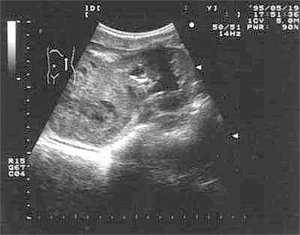

Эхография и РКТ позволяет значительно точнее определить анатомо-топографические и, в какой-то степени, морфологические характеристики нефробластомы (Рис. 1, 2). У всех наших пациентов опухоль была представлена объёмным образованием в виде солитарных масс преимущественно неправильной формы (95,2%). В области опухолевого узла контур почки был выпуклым (14,3%). В 50% обнаруживалась экзофитная зона с фрагментарно выраженной капсулой (71,4%). Эхографическая картина и изображение поражённой почки на РКТ были весьма схожи. Опухоль выглядела как негомогенная структура с преобладанием гиподенситивных очагов (90,5%). Эхографически кальцинаты при нефробластоме выглядят как редкие небольшие высокоинтенсивные сигналы и обнаруживались редко.

Рис. 2. Ультразвуковое сканирование опухоли почки (нефробластома) с очагами распада.

При эхографии опухоль выглядит как внутрипочечное эхогенное образование с достаточно чёткими контурами. Плотность образования выше, чем плотность паренхимы почек или даже печени. Оно более однородное и менее плотное, чем нейробластома, хотя и внутри опухоли Вильмса могут обнаруживаться неправильных очертаний гипоэхогенные очаги кровоизлияний, некрозов или расширенные чашечки.